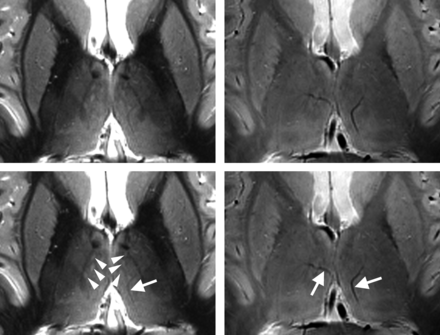

Figure 1 shows axial MR images through the thalamus at a position of about 10 mm dorsal to the ACPC plane, with the corresponding section of the atlas of Schaltenbrand and Wahren21 at position H.d +7.0. At first glance, a high degree of similarity between the IR-TSE image (TI = 500 ms) and the T1 map (calculated from a series of MR images with different TIs) is noticeable. However, more striking is the richness of visible anatomic detail in the lateral thalamus. For illustrative purposes, some salient landmarks are marked in white (Fig 1, bottom row). Arrowheads point to the mamillothalamic tract, paired arrowheads indicate the stria medullaris, and arrows point to the nucleus centre médian (Ce). The bold white line connecting the mamillothalamic tract and the most anterior part of the centre médian depicts the lamella medialis (La.m). Pairs of arrows point to a hypointense band between the mamillothalamic tract and the rostral border of the thalamus, separating the nuclei lateropolaris (Lpo) and anteromedialis (A.m) thalami. This structure, not explicitly assigned in the Schaltenbrand and Wahren atlas, is identified in the atlas of Mai et al22 as the internal medullary lamina, (ie, the myelin-rich sheet that largely corresponds to the La.m in the atlas of Schaltenbrand and Wahren21). The dotted and the thin white lines in Fig 1 mark well-defined signal-intensity transitions in the lateral thalamus. According to the corresponding section in the Schaltenbrand and Wahren atlas,21 we assigned the thin line to the border between the nuclei dorso-oralis internus (D.o.i) and externus (D.o.e) and the dotted line to the boundary between the D.o.i and the nucleus zentrolateralis intermedius internus (Z.im.i). Finally, the dashed lines designate a narrow hypointense band in the posterior thalamus separated by narrow hyperintense bands from the internal capsule and the lateral thalamic nuclei. We identify this dark band as the external medullary lamina and the hyperintense band between the external medullary lamina and the internal capsule as the reticulatum thalami (Rt). Although the latter 2 bands are clearly distinguishable, at least in the posterior half of the thalamus, in the Schaltenbrand and Wahren atlas21 they are subsumed under the Rt. In contrast, Mai et al22 differentiate the external medullary lamina and Rt in the posterior thalamus (frontal sections, plates 42–49, position 26.5–36.0 mm).

Display of MR and brain atlas images. An IR-TSE MR image (left column) and a T1 map (middle column) of the thalamus of a healthy subject and the corresponding axial section from the Schaltenbrand and Wahren atlas for Stereotaxy of the Human Brain,21 including an illustrative sketch (right columns, plate LXXVIII H.d +7.0). Reproduced with permission from Thieme Medical Publishers. To facilitate comparison, the images are scaled so that thalami exhibit comparable sizes in the anteroposterior direction. The MR images were acquired with a resolution of 0.52 × 3 mm3 (left column) and 0.62 × 3 mm3 (middle column). In the bottom row, which is identical to the top row, note the following structures: Bold lines mark the lamella medialis (La.m), thin lines mark the border between the internal and external part of the nucleus dorso-oralis (D.o.i and D.o.e), dotted lines show the border between the internal parts of the nuclei dorso-oralis (D.o.i) and zentrolateralis intermedius (Z.im.i), dashed lines indicate the posterior part of external medullary lamina, arrows point to the centre médian (Ce), arrowheads indicate the mamillothalamic tract, paired arrowheads indicate the stria medullaris, and pairs of arrows indicate a myelinic sheet separating the nuclei lateropolaris (Lpo) and anteromedialis (A.m). Note the very similar contrast in the IR-TSE image (TI = 500 ms) and the T1 map.